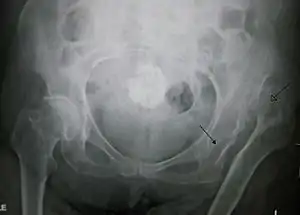

| X-ray showing a joint dislocation of the left hip. | |

Typically, people with hip dislocations present with severe pain and an inability to move the affected leg.[1][4] Diagnosis is made by physical exam and plain X-rays of the hips. A CT scan is recommended following reduction to rule out complications. Complications include osteonecrosis, femoral head fractures, and posttraumatic osteoarthritis.[12][13]

An anterior-posterior (AP) X-ray of the pelvis and a cross-table lateral X-ray[24] of the effected hip are ordered for diagnosis.[4][5][16] The size of the head of the femur is then compared across both sides of the pelvis. The affected femoral head will appear larger if the dislocation is anterior, and smaller if posterior.[7] A CT scan may also be ordered to clarify the fracture pattern.[19]